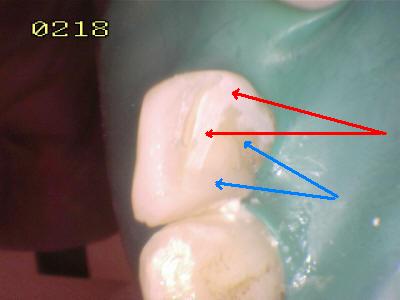

Grabado con ácido ortofosfórico

Flechas rojas: Esmalte grabado   Flechas azul resina compuesta